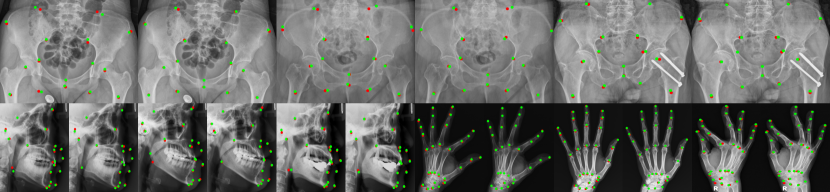

4.4 Graph Structure Visualization

To better understand learning outcomes, we look into the visualization on the learned graph structure. As shown in Figure 3, the learned structures in different domains are meaningful indicating strong connections between 1) spatially close landmarks, and 2) remote but related landmarks that move coherently, e.g. symmetrical body parts. We believe the mechanism behind our algorithm is relying on these locations to provide reliable inductions when it makes movement predictions, such as similar movements by neighbors, or fixed spatial relationships by the symmetrical body parts (e.g., eyes, pelvis). With the learnable graph connectivity, we are able to capture the underlying landmarks relationships for different objects.